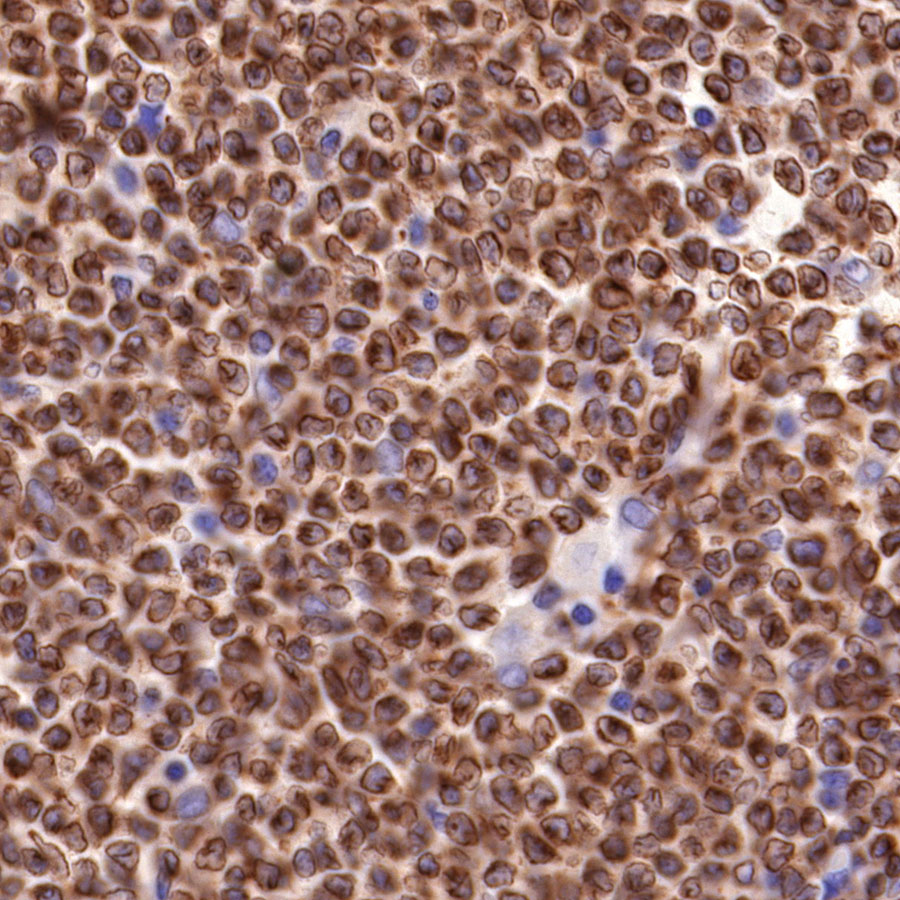

Picture

Immunohistochemistry